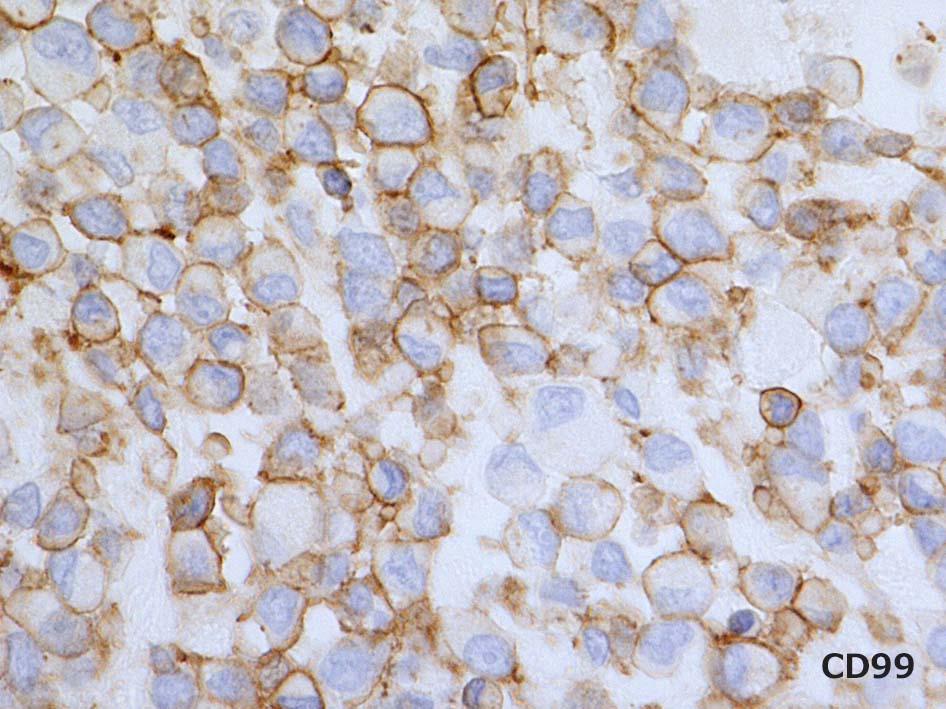

Vimentin, CD99(MIC2)はびまん性に陽性を示す. CD34はfocalに陽性. 異型 spindle cellにも陽性を呈する. EMAは少数の陽性細胞あり. BCL2はリンパ球に陽性. 腫瘍細胞はほぼ陰性. 淡く染まる細胞がごく少数ある. CK(AE1/3)は陰性. p53はびまん性, 80%に陽性. (photo準備中). MIB-1 LIは>90%.

BRG1は核染色性が消失. internal controlの血管内皮や炎症細胞は核に陽性となる. INI1(SNF5/SMARCAB1)はびまん性に陽性. p53が多くの腫瘍細胞に陽性となる.

phenotype: 免疫染色の所見.

文献; Or(Le Loarer, et al*1), J(Japanese cases*2), F(French cases*4), A(American-Mayo,etc cases*3)

診断に必須と考えられる免染結果

その他陽性を示す抗体

陰性所見の免疫染色